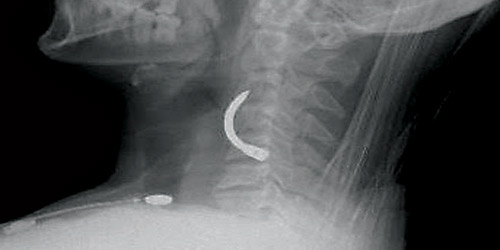

أنقذ فريق متخصص بمركز الإصابات بمدينة الملك سعود الطبية بعد عناية الله سبحانه حياة مقيم ، حينما اخترق رقبته مسماراً حديدياً، أثر قيامه بأعمال بناء.

وقد تمكن الفريق الطبي من استخراج المسمار الحديدي الذي يبلغ طوله 8 سم، بعدما كان يعمل على تثبيت مسمار البناء ، وارتد إلى رقبته . وقد أجرى الفريق الطبي قبل استخراجه المسمار عملية استكشاف لرقبة المصاب وأتضح أنه كان على بعد مسافة قريبة من الشريان السباتي الذي يؤدي قطعة لفقدان الحياة . وأوضح الفريق الطبي بأن العملية استغرقت ساعة ونصف، والمريض الآن بصحة جيدة ولله الحمد، ويستعد للخروج خلال اليومين القادمة .